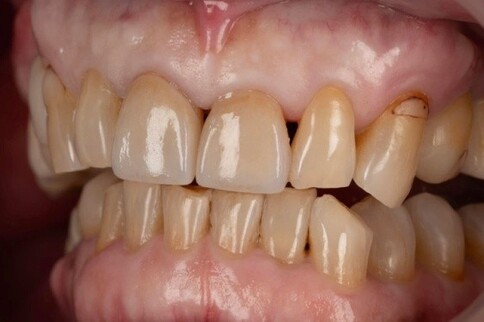

Case 5:年長患者磨耗裂痕修復,稍稍提亮。